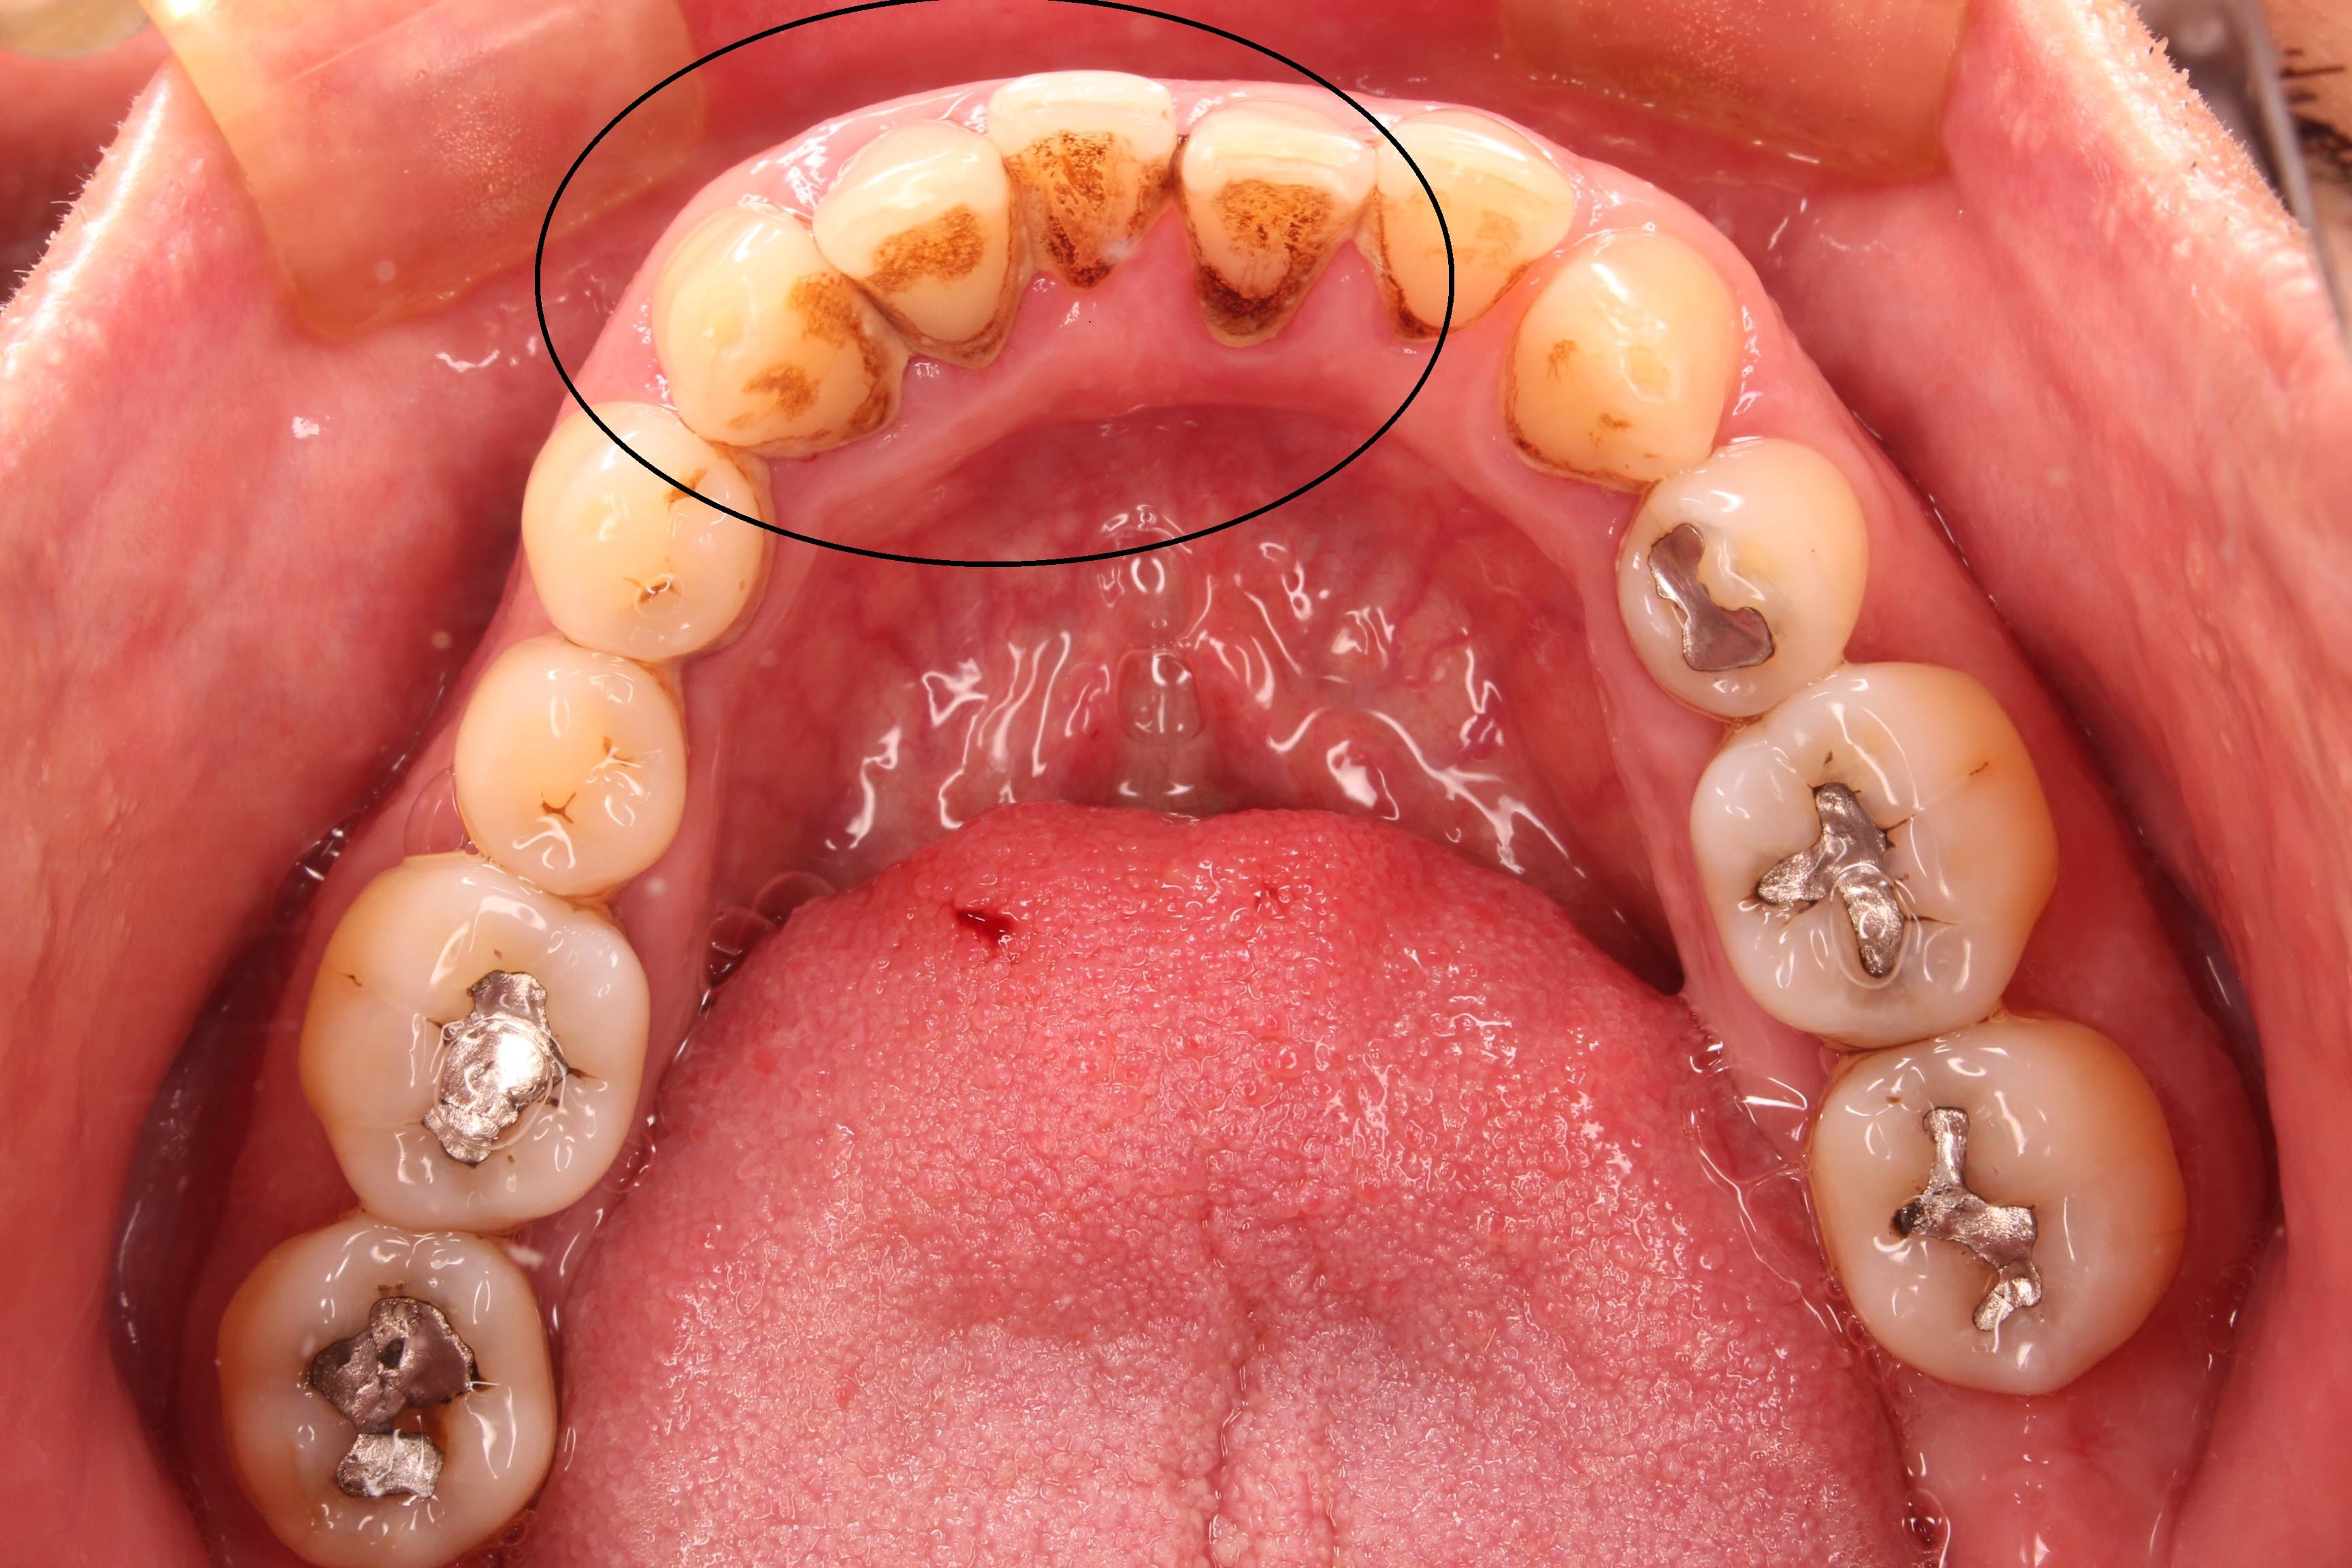

今回ご紹介する歯周病専門治療のケースは、60代男性の方です。

40年前に虫歯の治療をして以来、自覚症状のある問題は起きなかった為、歯科医院へは行っていなかったそうです。

しかし、今回詳しく検査をしてみると、写真でもはっきりとわかるように、歯石やプラーク、ステインなど感染物が大量に付着しています。

またレントゲン検査においては、歯周病により、歯槽骨が部分的に2/3以上破壊されていました。